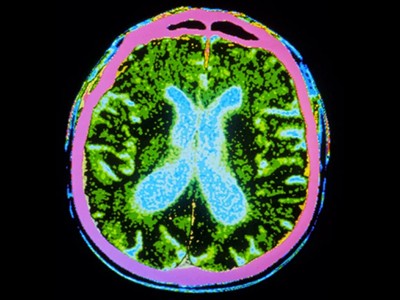

截至去年12月,共有83種源自多能干細(xì)胞的產(chǎn)品正在進(jìn)行115項(xiàng)臨床試驗(yàn)。帕金森病的治療方法比任何其他中樞神經(jīng)系統(tǒng)疾病的治療方法都處于更先進(jìn)的發(fā)展階段。帕金森病的特征是釋放神經(jīng)遞質(zhì)分子多巴胺的神經(jīng)元逐漸喪失。帕金森病相關(guān)的運(yùn)動(dòng)癥狀,例如肌肉僵硬、運(yùn)動(dòng)遲緩、震顫和步態(tài)障礙,都是由中腦黑質(zhì)區(qū)域神經(jīng)元的耗竭引起的。

帕金森病是由于大腦中釋放多巴胺(多巴胺能)神經(jīng)元逐漸喪失所致。Sawamoto 等人1和 Tabar 等人2進(jìn)行了一項(xiàng)基于干細(xì)胞治療的臨床試驗(yàn)。兩個(gè)團(tuán)隊(duì)都使用了臨床級(jí)多能干細(xì)胞來(lái)補(bǔ)充多巴胺能神經(jīng)元,這種細(xì)胞可以無(wú)限分裂并分化為任何細(xì)胞類(lèi)型。Sawamoto等人使用了源自健康成年捐贈(zèng)者細(xì)胞的誘導(dǎo)多能干細(xì)胞系,而Tabar等人使用了源自早期胚胎的人類(lèi)胚胎干細(xì)胞系。干細(xì)胞經(jīng)過(guò)培養(yǎng),形成多巴胺能神經(jīng)元祖細(xì)胞。這些細(xì)胞被移植到稱(chēng)為殼核的大腦區(qū)域,殼核與尾狀核一起形成紋狀體。紋狀體與黑質(zhì)相連,而黑質(zhì)是多巴胺能神經(jīng)元損失最為嚴(yán)重的部位。早期(I/II期)臨床試驗(yàn)主要證實(shí)了該療法的安全性,同時(shí)也表明其在改善癥狀方面具有一定有效性。